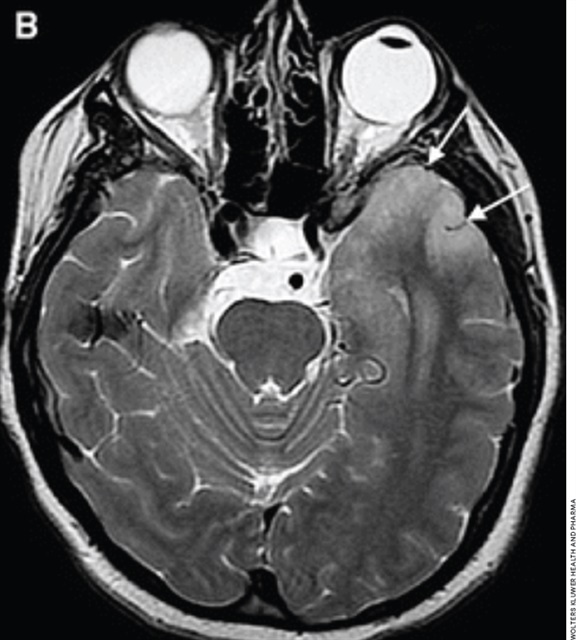

A recent study published in JAMA Neurology found that early treatment results in the best outcomes for NMDA receptor encephalitis. bit.ly/3CRiQ3s #NMDARE #NeuroTwitter

Love this graphic of all the findings associated with CAA #neurotwitter #stroke Stroke: Vascular and Interventional Neurology Stroke AHA/ASA Emory & Grady Neurocritical Care Fellowship Jay Kinariwala Neha Dangayach MD MSCR FAAN FANA FCCP FCCM FNCS Edip Gurol Juan Carlos Martinez Gutierrez MD Feras Akbik Shivani Ghoshal